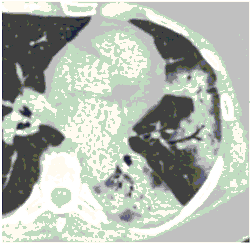

2. Наличие клинических проявлений, указанных в п. 1, в сочетании с характерными изменениями в легких по данным компьютерной томографии (КТ) (см. Приложение 1 настоящих рекомендаций) вне зависимости от результатов однократного лабораторного исследования на наличие РНК SARS-CoV-2 и эпидемиологического анамнеза.

- Изменения при КТ (рентгенографии), типичные для вирусного поражения (объем поражения минимальный или средний; КТ 1-2)

- Изменения в легких при КТ (рентгенографии), типичные для вирусного поражения (объем поражения значительный или субтотальный; КТ 3-4)

- Изменения в легких при КТ (рентгенографии), типичные для вирусного поражения критической степени (объем поражения значительный или субтотальный; КТ 4) или картина ОРДС.

КТ имеет высокую чувствительность в выявлении изменений в легких, характерных для COVID-19. Применение КТ целесообразно для первичной оценки состояния ОГК у пациентов с тяжелыми прогрессирующими формами заболевания, а также для дифференциальной диагностики выявленных изменений и оценки динамики процесса. КТ позволяет выявить характерные изменения в легких у пациентов с COVID-19 еще до появления положительных лабораторных тестов на инфекцию с помощью МАНК. В то же время, КТ выявляет изменения легких у значительного числа пациентов с бессимптомной и легкой формами заболевания, которым не требуется госпитализация. Результаты КТ в этих случаях не влияют на тактику лечения и прогноз заболевания при наличии лабораторного подтверждения COVID-19. Поэтому массовое применение КТ для скрининга асимптомных и легких форм болезни не рекомендуется.